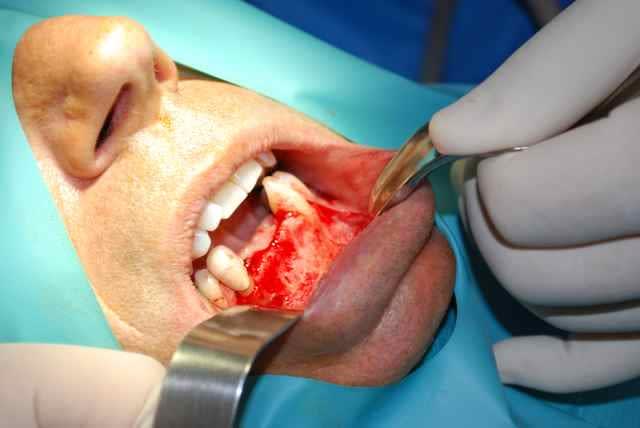

bonjour, ce cas d expansion est superbe, on peut pas toujours et cette situation clinique avec une crete hyperfine +concavite juste en dessous mais plus de nonosse plus bas m a fait preferer une petite greffe classique, facile puisque une seule zone deonneuse receveuse.les implants prevus dans 5 mois.

pour suturer pas de problemes de plans -le lambeau part du sulcus des dents et dans ce cas precis au milieu de la crete edentee. pour les prelevements symphysaires je suis les conseils des "anciens" et je prefere sauf contre indications faire une incision niveau sulcus ; c est a peine plus long pour le decollement mais les fibres musculaires sont dans le lambeau et jusqu a present peu de suites post op.

le repositionnement du lambeau est simple et qq sutures simples suffisent.

les complications que j'ai rencontrees sont essentiellement au niveau des sites receveurs a la mandibule avec des petites expositions tardives au niveau des vis . au niveau du ramus , plutot de l' oedeme post op essentiellement mais des greffons plus longs et essentiellement du cortical donc interessant au maxillaire en apposition, une meilleure acceptation du site pour le patient qui peut faire l analogie avec une dds.

j ai fait qq prelevements au piezo sur la symphyse et c est tres econome d'os mais j'ai trouve que c etait trop long compare a une fraise fissure qui prend qq minutes, au ramus par contre les inserts coudes sont super pour la tranchee inf.

jai utilise aussi la scie oscillante-voir fichier joint- mais vu les vibrations plus jamais sous locale, bloc seulement , c est trop de stress pour le patient.